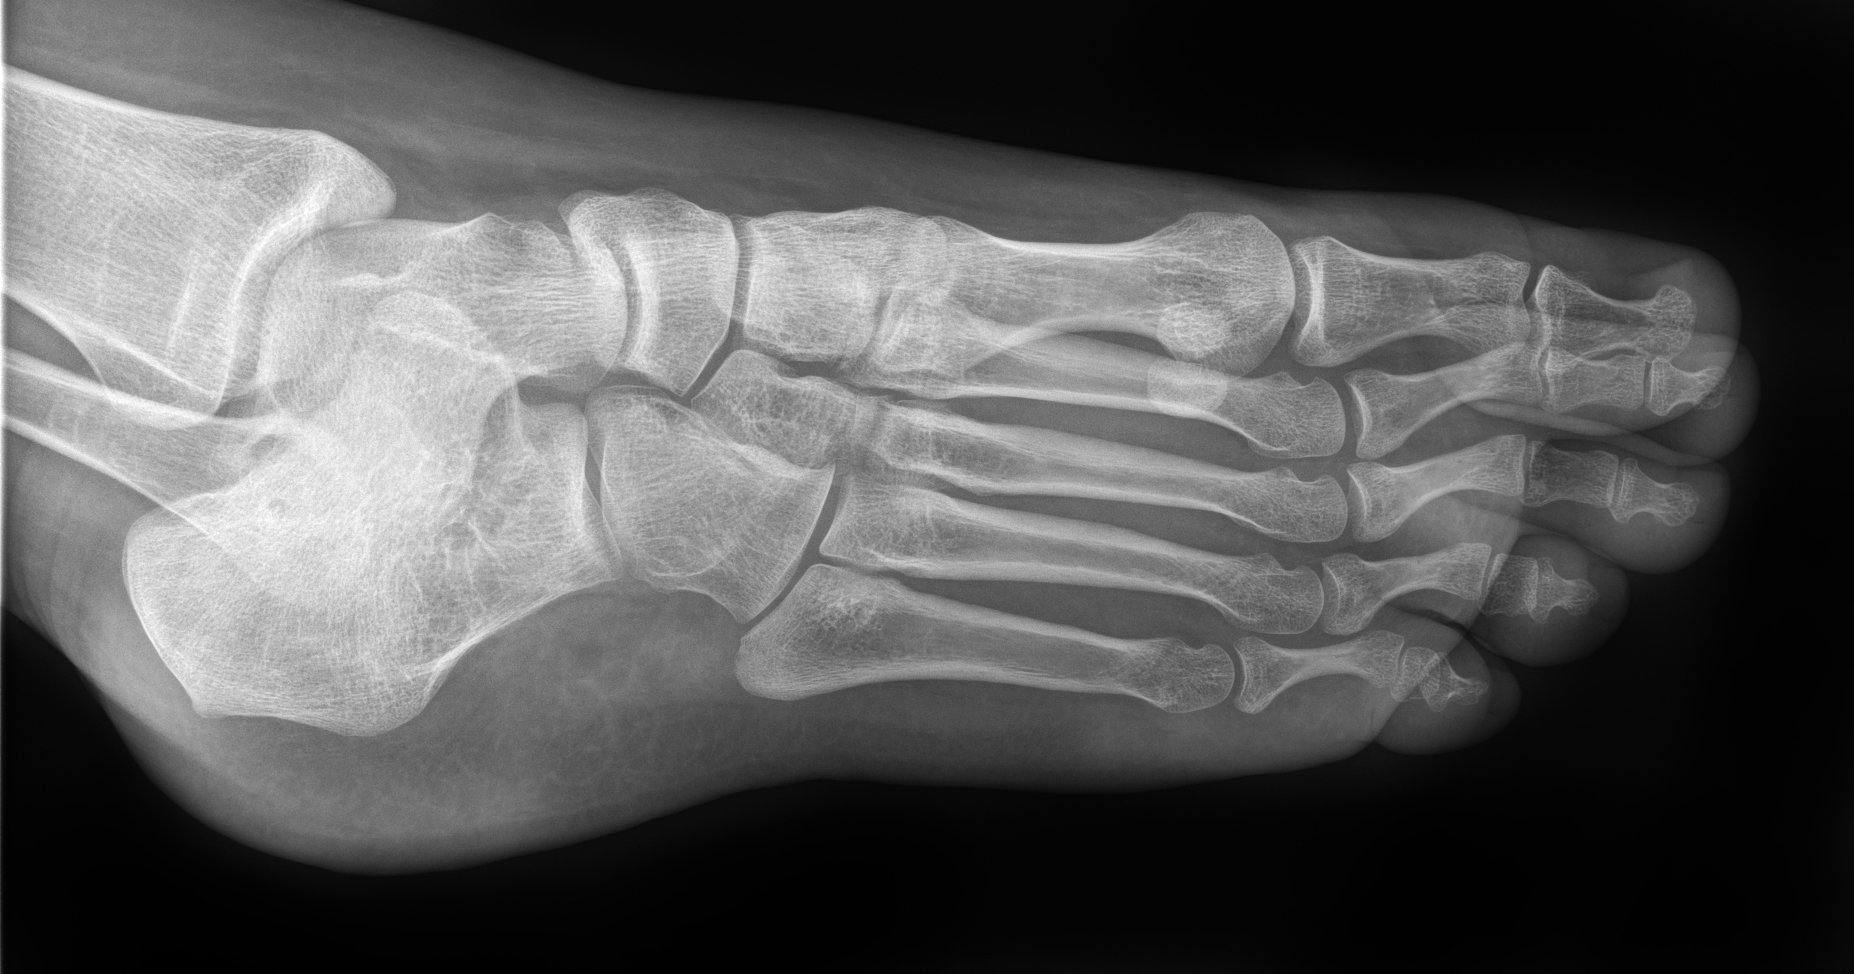

Defining Practice - 3D Scoliosis Spine